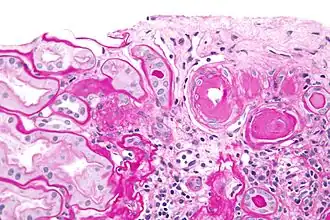

Histopathology

Hyaline cartilage is named after its glassy appearance on fresh gross pathology.[3] On light microscopy of H&E stained slides, the extracellular matrix of hyaline cartilage looks homogeneously pink, and the term "hyaline" is used to describe similarly homogeneously pink material besides the cartilage. Hyaline material is usually acellular and proteinaceous. For example, arterial hyaline is seen in aging, high blood pressure, diabetes mellitus and in association with some drugs (e.g. calcineurin inhibitors). It is bright pink with PAS staining.